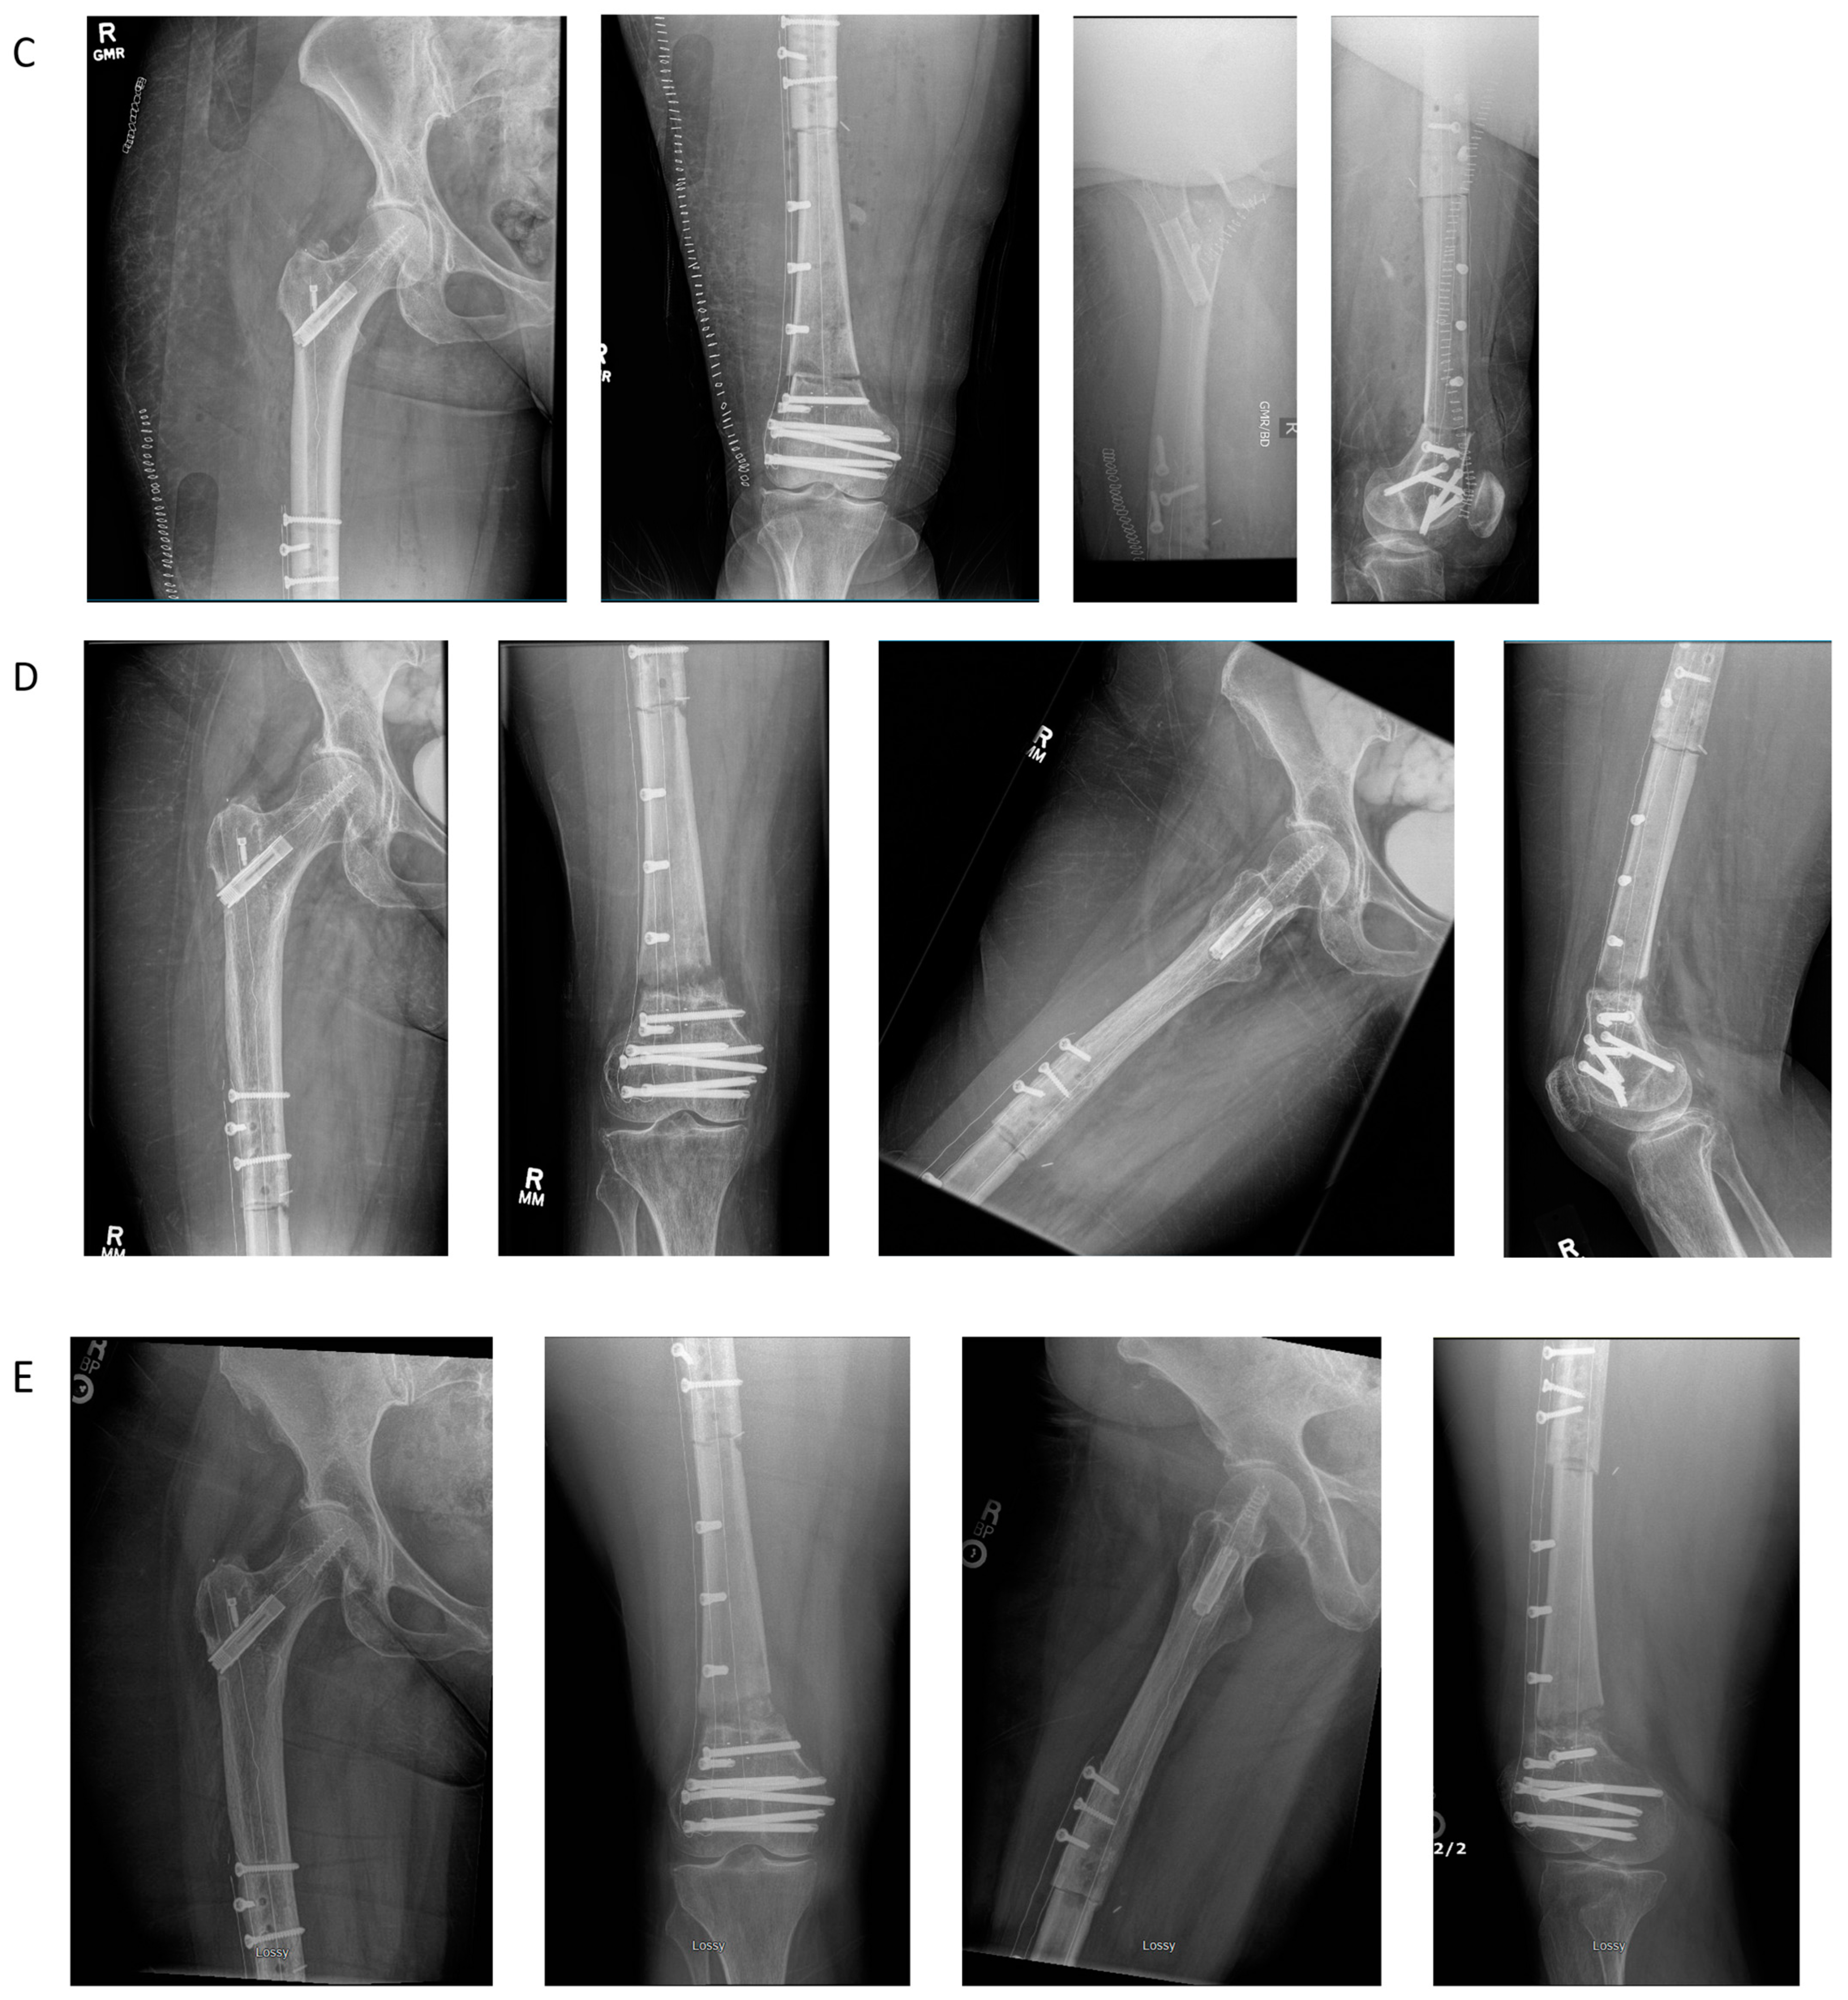

4.5. Case Example 5—Revision Plate and Nail Fixation with Fibular Autograft Augmentation of Prior Tibial Intercalary Allograft Failure